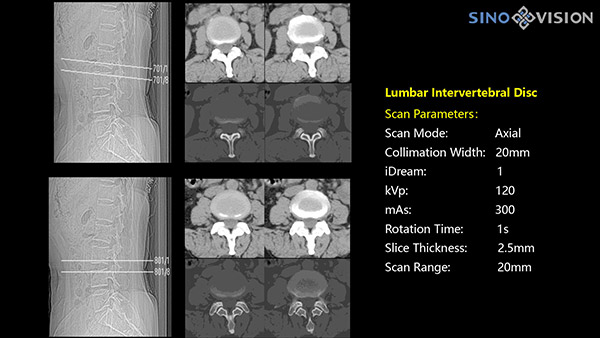

Инновационный 128-срезовый компьютерный томограф SinoVision InsitumCT 568 – это сочетание высокой скорости работы, низкой дозы и максимума возможностей для подавляющего большинства клинических случаев, как в рутинных, так и в углубленных специализированных исследованиях, в том числе педиатрические и кардиологические исследования при сверхнизких дозах.

Полнофункциональный 128-резовый компьютерный томограф InsitumCT 568 - это лучшее в новом поколении широкодиапазонных томографов с 128 срезами и большой диафрагмой. Этот КТ-сканер с большой апертурой обеспечивает 128 срезов КТ с диафрагмой 76 см, улучшает разрешение изображения до 21Lp/cm, помогает точно диагностировать и лечить заболевания, а также значительно улучшает клинические характеристики и расширяемость оборудования. Позволяет реализовать визуализацию в высоком разрешении и в малых дозах лучевой нагрузки.

Полнофункциональная платформа клинической диагностики может точно определять местонахождение и диагностировать общие повреждения качественно и количественно, а также достигать полнофункциональных клинических показателей, включая обширные кардиологические исследования со сверхнизкими дозами лучевой нагрузки.